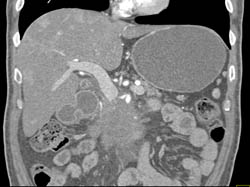

Diagnosis

Gastrostomy Tube